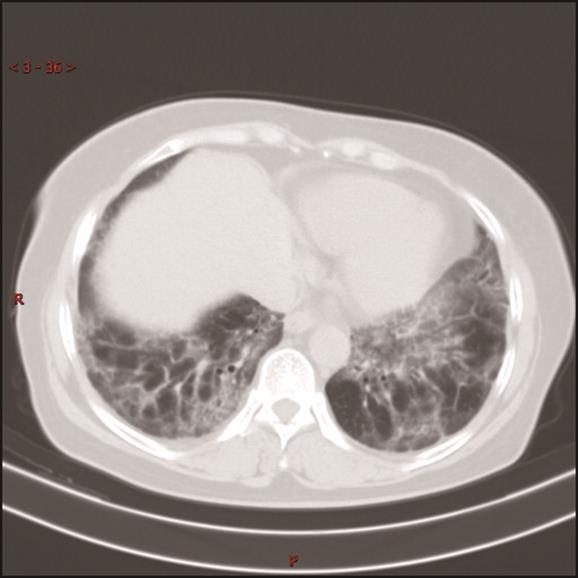

摘要:目的 探究显微镜下多血管炎(microscopic polyangiitis,MPA)肺受累的临床特征与预后因素分析。方法 回顾性分析2014年1月1日至2021年3月1日于重庆医科大学附属第一医院确诊及随访至2022年3月1日的237例MPA肺受累患者临床资料。采用Kaplan-Meier方法和Cox比例风险回归模型分析生存数据,得出累积生存率及预后因素。结果 MPA肺受累患者的平均年龄是65.18岁,中位随访时间为26.13个月。在纳入研究的237例患者中,MPA伴弥漫性肺泡出血(diffuse alveolar haemorrhage,DAH)患者98例(41.35%)。MPA肺受累患者1年、3年、5年累积生存率分别为67.50%、54.10%、43.00%。中位生存时间为45.03(0.10,97.73)个月。MPA伴DAH患者1年、3年、5年累积生存率分别为63.30%、49.40%、40.20%。Cox多因素回归分析显示年龄>65岁(HR=1.981,95%CI=1.244~3.154,P=0.004)、白细胞总数(white blood cell,WBC)>10×109个/L(HR=1.860,95%CI=1.170~2.956,P=0.009)、血清肌酐(serum creatinine,sCr)>250 μmol/L(HR=1.987,95%CI=1.217~3.243,P=0.006)、氧合指数<300 mmHg(HR=2.780,95%CI=1.696~4.557,P<0.001)、诊断时第三版伯明翰血管炎活动性评分(Birmingham vasculitis activity score version 3,BVASv.3)(HR=1.040,95%CI=1.006~1.075,P=0.020)是影响患者生存时间的独立预测因素(P<0.05)。结论 MPA肺受累患者生存率低下,年龄>65岁、WBC>10×109个/L、sCr>250 μmol/L、氧合指数<300 mmHg、诊断时BVASv.3是MPA肺受累预后不良的独立危险因素。